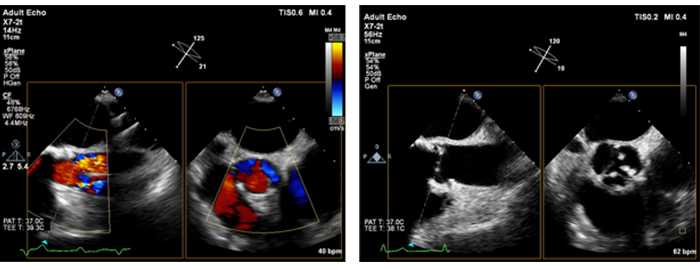

Live xPlane imaging in xMATRIX ultrasound Creates two full-resolution planes simultaneously, allowing you to capture twice as much clinical information in the same amount of time as conventional 2D imaging.

During your cardiac exams, live xPlane imaging allows you to acquire two planes simultaneously from the same heartbeat, capturing critical information quickly and confidently.